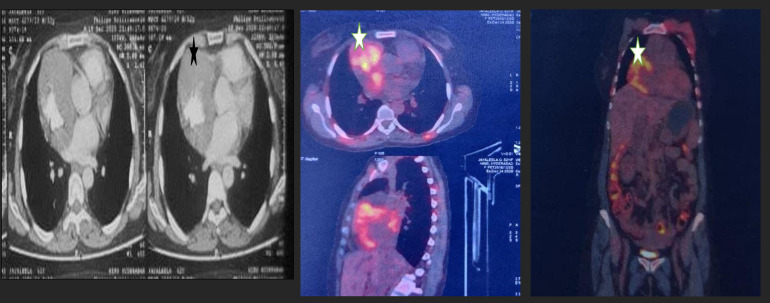

Immunoglobulin G4-related disease (IgG4-RD) coexisting with clinically apparent autoimmune diseases, such as rheumatoid arthritis (RA) or antiphospholipid syndrome (APS), is a rarely documented combination in the scientific literature. In this case-based review, we present 2 intriguing cases with preexisting autoimmune diseases, namely, RA and primary APS, who exhibited coexistent IgG4- related lesions at unusual sites. The first case pertains to a patient with known RA who presented with an encasing mass in the esophagus leading to stricture, with histopathological diagnosis of IgG4-RD.The second patient, diagnosed with primary APS, experienced breathlessness, and imaging revealed a right atrial mass. Histopathological examination of the mass confirmed IgG4-RD. Notably, both patients demonstrated significant clinical improvement upon initiation of steroid therapy. Rheumatoid arthritis patients commonly exhibit elevated levels of IgG4 in their sera; however, RA with coexisting IgG4-RD is rarely reported in the literature. Similarly, APS with IgG4-related lesions is exceedingly rare. Although there are few case reports and series on esophageal and cardiac IgG4-RD, the occurrence of such unusual location of IgG4-related lesions in the context of known autoimmunity is presented here for the first time.